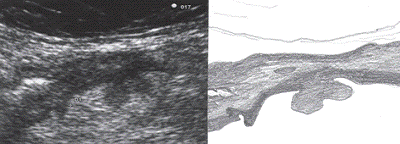

Наиболее информативным методом

выявления дивертикулеза толстой кишки является исследование толстой кишки с

помощью бариевой клизмы (ирригоскопия). При неосложненном дивертикулезе

кишечная стенка имеет неровный контур и образует мешковидные выпячивания по ее

контуру, имеющие суженное основание (устье). Размеры этих выпячиваний

колеблются от 0,2-0,3 до 1-2 см, чаще в сигмовидной и нисходящей ободочной

кишках. Для выявления дивертикулов иногда необходимы снимки в боковой проекции.

Обращают внимание на тонус кишки, глубину межгаустральных складок, а также

растяжимость и эластичность кишечной стенки. Ирригоскопия позволяет выявить

смещаемость отделов ободочной кишки или, напротив, их фиксацию вследствие

паракишечного воспалительного процесса.